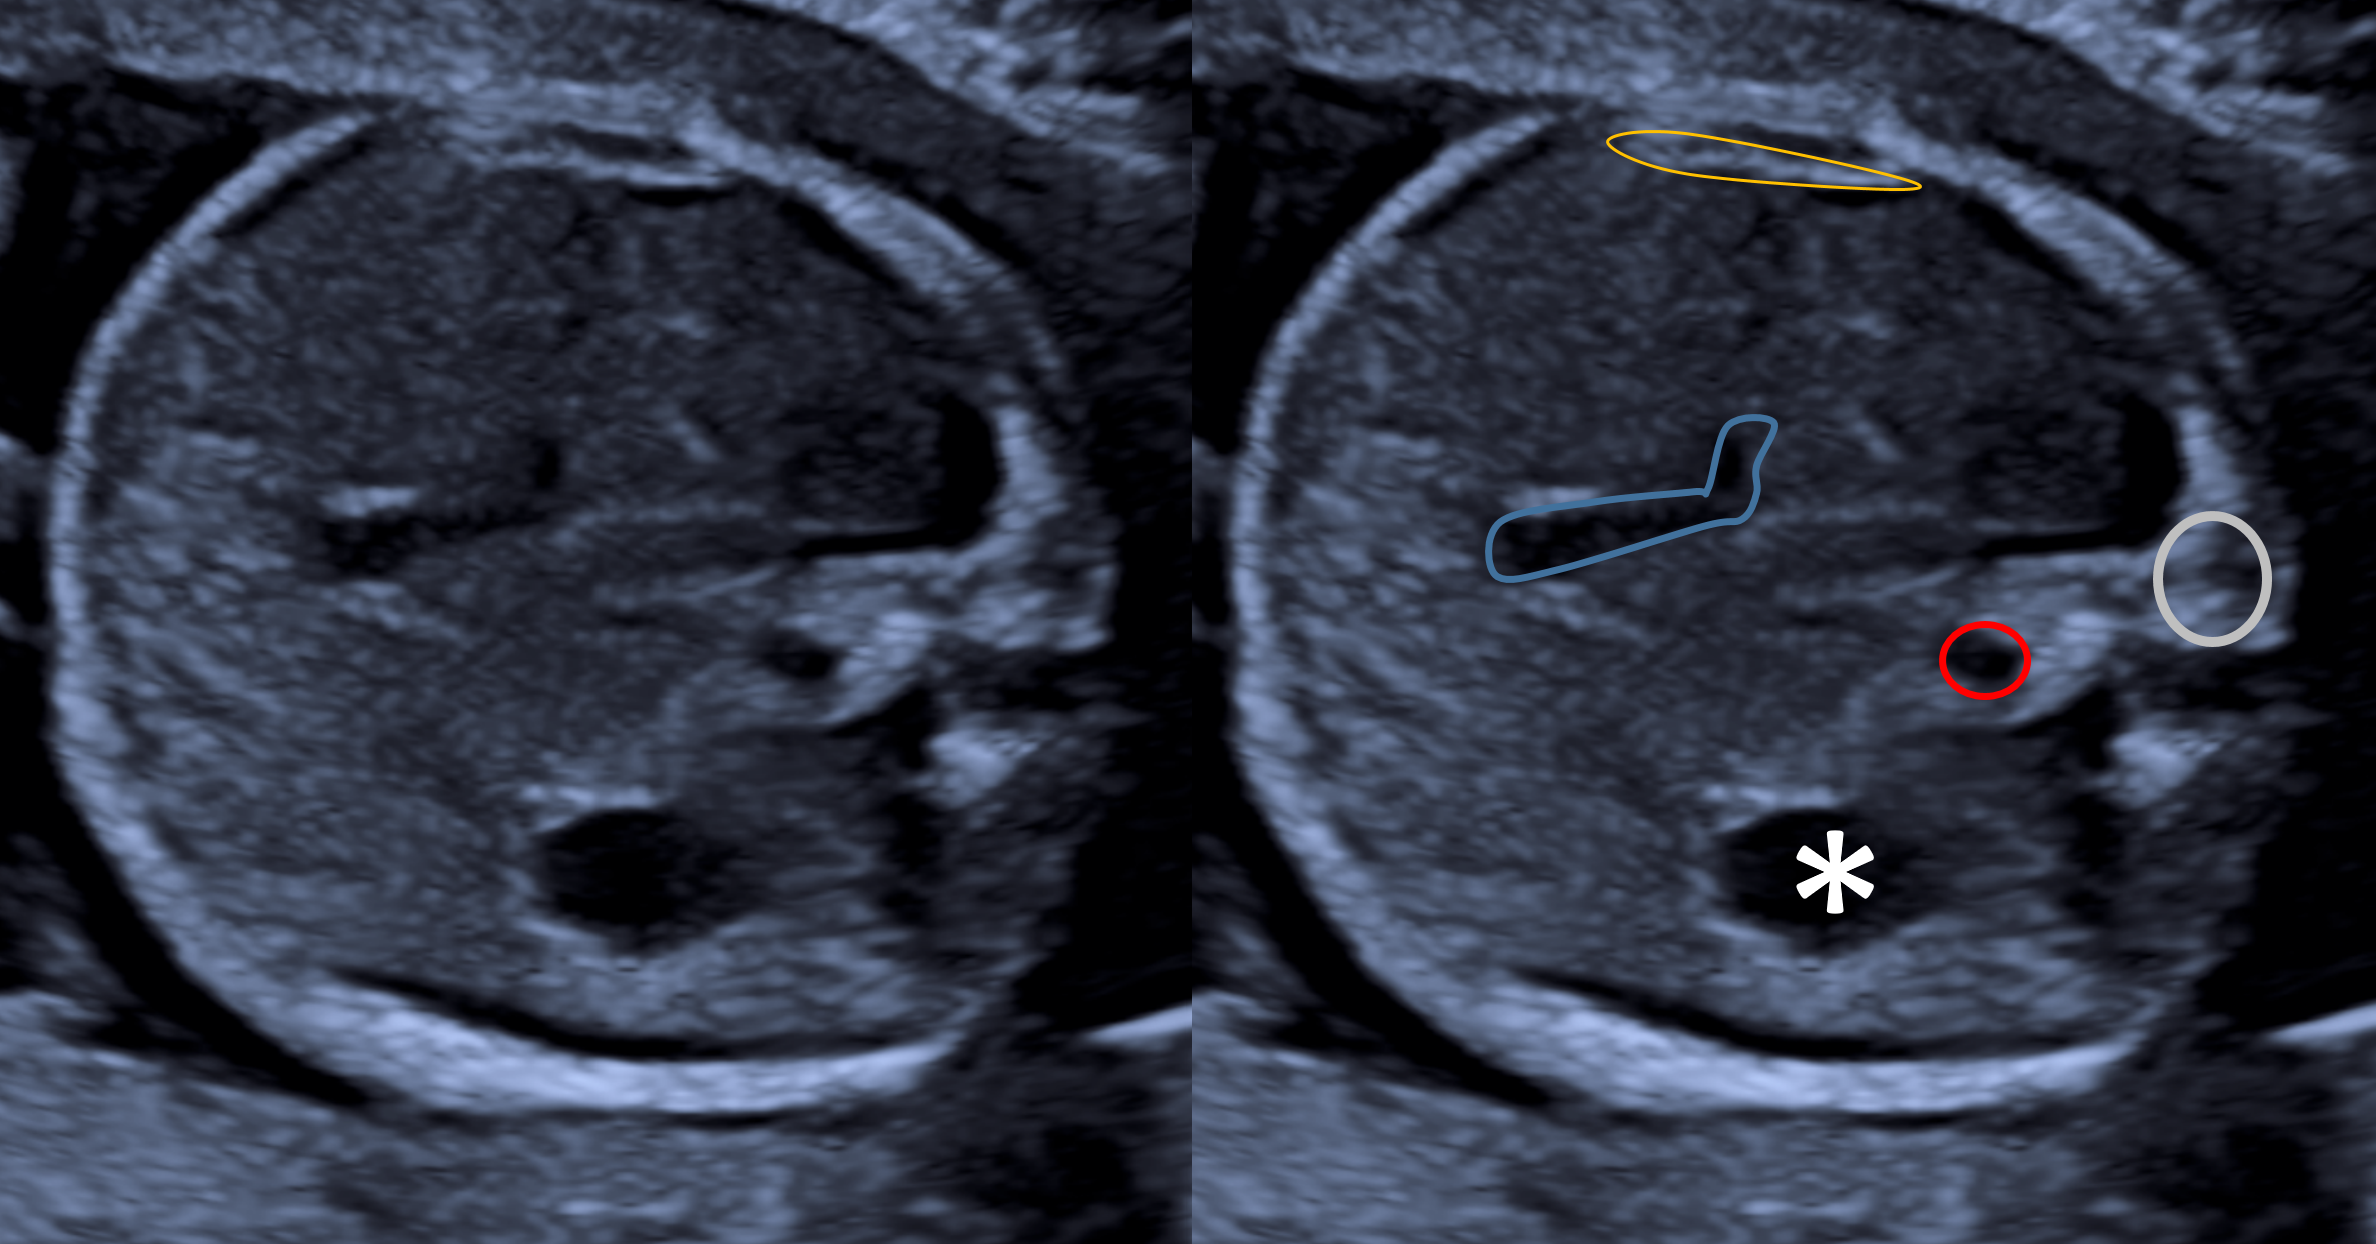

CIrcCefal_Aula_BiometriaCorte axial ultrassonográfico do crânio fetal, adequado para a medida dos diâmetros biparietal (DBP) e occipitofrontal (DOF). A circunferência cefálica (CC) pode ser obtida diretamente por traçado elíptico neste plano ou calculada automaticamente pelo equipamento a partir do DBP e do DOF. Rosa: tálamos. Azul: terceiro ventrículo. Amarelo: cavum do septo pelúcido. Vermelho: linha média inter-hemisférica (foice cerebral). Verde: contorno da porção parietal do ventrículo lateral. Branco: plexo coroide. Asterisco: ausência do cerebelo, confirmando plano adequado para biometria cefálica.